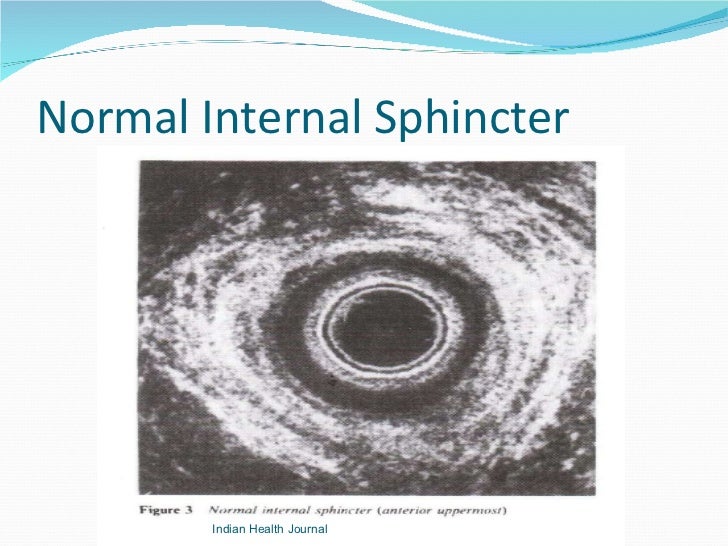

Hypertonicity esophageal anal sphincter